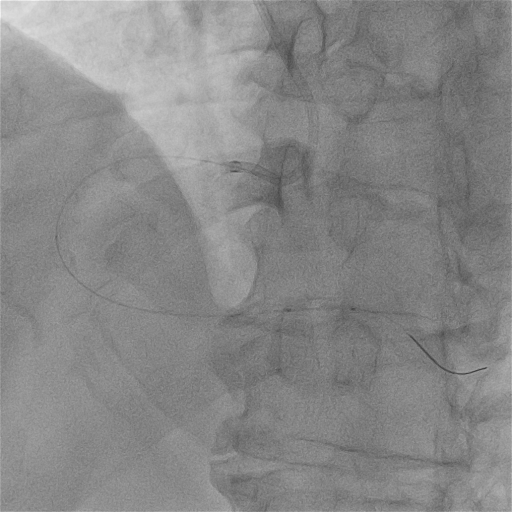

最终CAG和IVUS

术后造影及IVUS可见支架膨胀及贴壁良好,支架远近端未见夹层血肿。